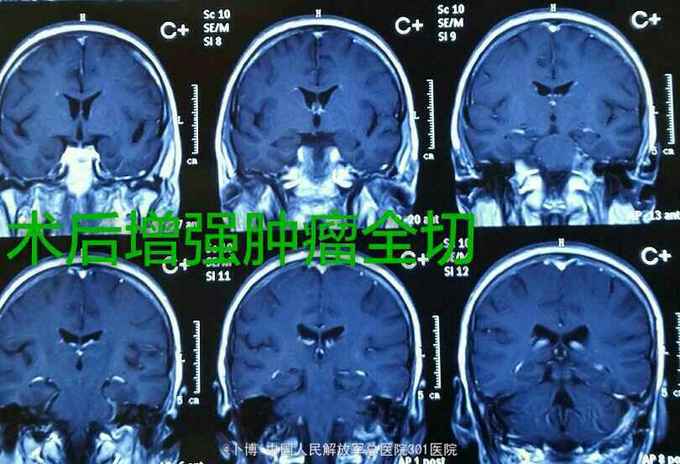

诊断:左侧岩斜脑膜瘤。 手术:乙状窦后入路。肿瘤位于面听神经的前方,将三叉神经根推向内侧。为了扩大显露并彻底切除肿瘤(基底),磨除了部分道上结节的骨质。 肿瘤全切。面听神经及三叉神经保留。

术后三个月复查。肿瘤全切。患者有面部麻木,疼痛消失。有轻度面瘫。听力尚存。